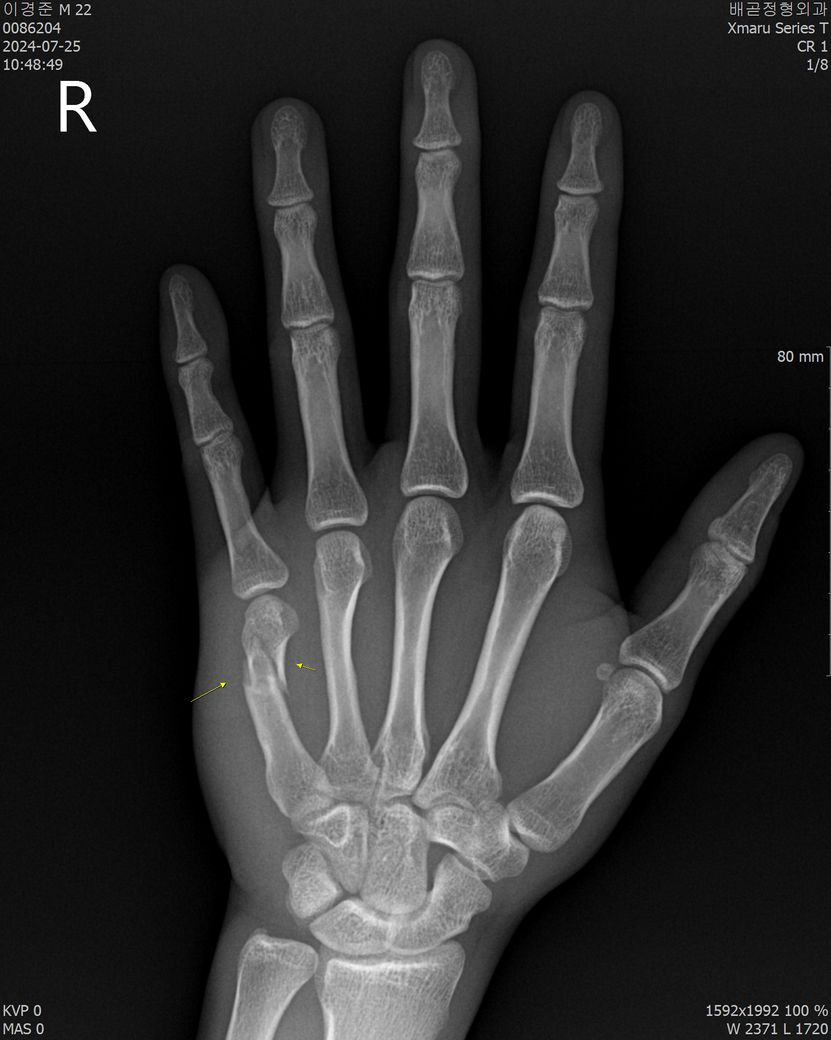

중수골 목의 골절 폐쇄성 수술해야할까요?

정형외과에서 뼈 맞추고 현재 깁스하고있는 상태입니다

근데 의사선생님께서 수술을 하는 편이 예후에 좋을수있다라고 하셔서 질문드립니다.

• 1번 째 사진

• 2번 째 사진

현재 상태로는 수술을 권유 할 수 있는 단계로도 보입니다만 이건 주치의와 영상 판독에 따라 결과가 다를 수 있습니다.

보통 중수골의 골절 상태를 보고 보존적 치료 (깁스, 고정)을 해서 경과를 지켜보기도 합니다.

골절이라고해서 무조건적으로 수술이필요한건아닌데요 지속적으로 불편감이있다면 수술적치료가필요할수있고 엑스레이상으로볼때에는 수술적치료가 필요해보이기는하나 좀더자세한건 병원에서 전문의와 상담을받아보는것이 좋습ㄴ디ㅏ

중수골 골절이 폐쇄성일 경우 수술 여부는 골절의 위치와 상태에 따라 다릅니다 수술이 필요한 경우는 뼈가 많이 어긋나거나 불안정한 경우로 의사 께서 옣를 고려해 권장하신것일 수 있어요 깁스를 하고 약을 먹으며 정기적인 병원 방문을 통해 회복 상태를 점검하는 것이 중요합니다!

중수골 골절 같은경우 교정이후 석고고정으로도 골유합이 잘되는 뼈이지만 불유합이 생기는 경우에는 수술적인 치료가 예후가 좋습니다.

1. 뼈가 어긋날정도의 골절이라서 2. 수술하시는게 좋아 보입니다. 3. 다음 예약은 해당병원에 문의하셔서 잡는게 좋습니다

• 수술을 하는편이 아무래도 alignment를 유지하기에 좋습니다.

• 수술을 고려해보시는 편이 좋습니다.